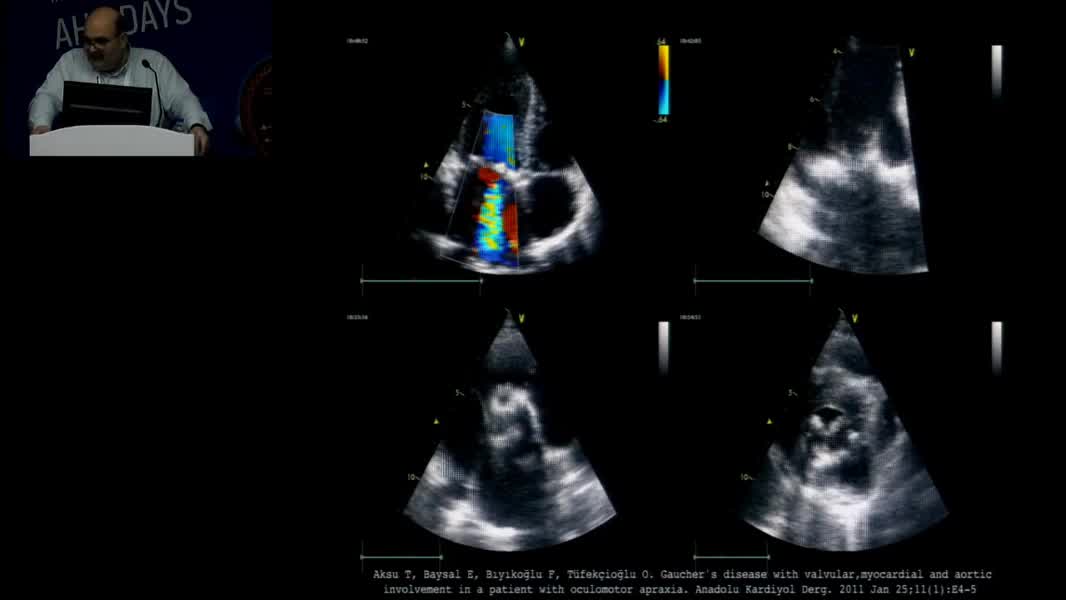

Echocardiographic Face Of Rare Cardiomyopathy And Fabry: Hands On Practical Echocardiography Course In The Diagnosis Of Fabry Disease And Cardiomyopathy Omaç Tüfekçioğlu (TR)

Nadir Miyokardiyopati ve Fabry’nin Ekokardiyografik Yüzü